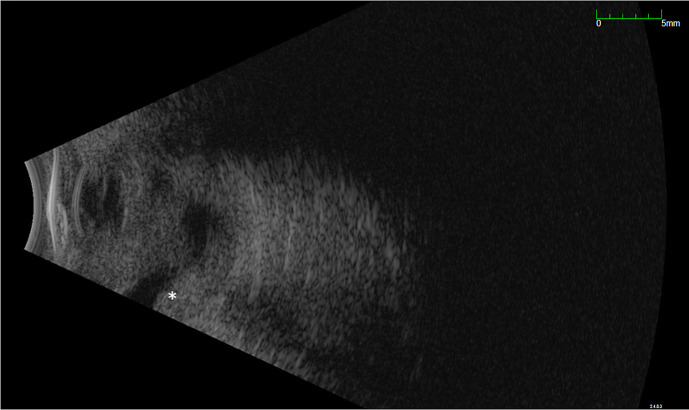

Case presentation: An 11-month-old female presented with poor visual behavior since birth and an intraocular mass in the left eye. Examination under anesthesia revealed a detached retina rolled into a stalk attached to the optic nerve in the right eye and a white retrolental mass with perfused vessels in the left eye. Magnetic resonance imaging demonstrated a heterogeneous mass filling the left globe with diffusion restriction and contract enhancement. Aqueous humor liquid biopsy was performed in both eyes with low DNA yield and no mutations associated with retinoblastoma were identified. The patient was observed with no interval change in examination for 6 months.